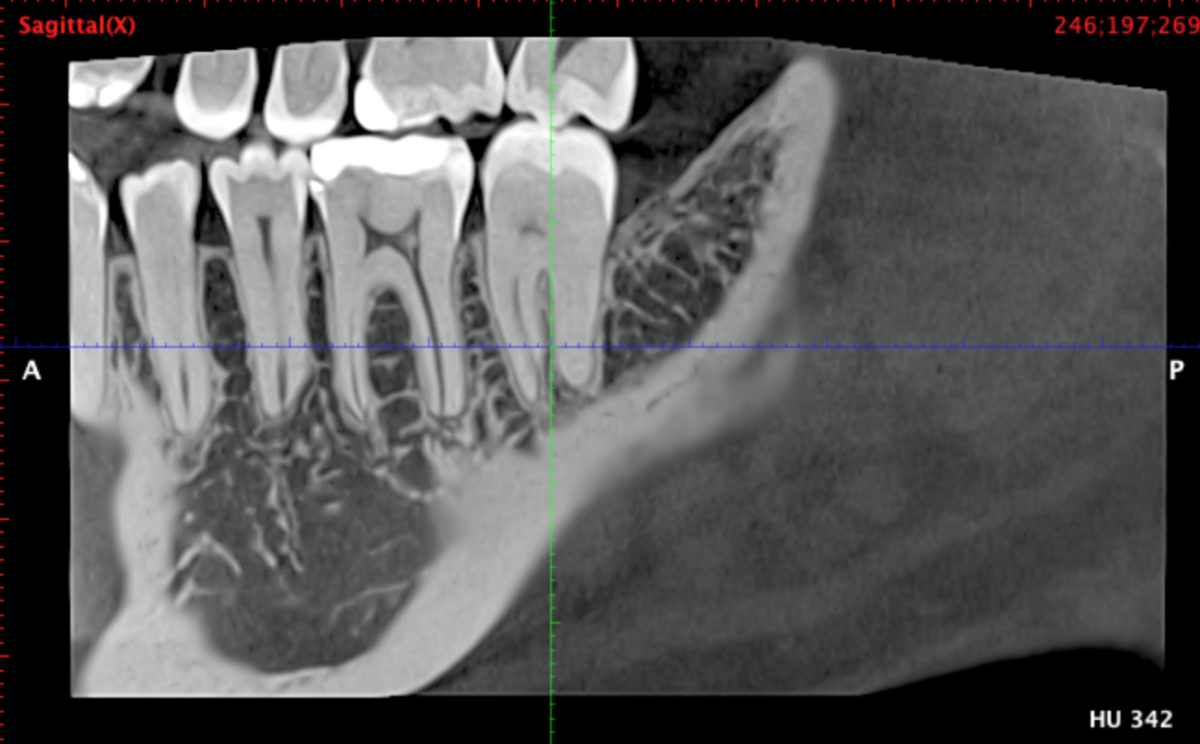

Я сделал клкт сектора 4-5-6-7 зубов справа снизу, могу приложить, если нужно. Я проходил ортодонтическое лечение, после которого у меня случилась рецессия десны на передних нижних зубах, вплоть до клыков. На самом оголоенном участке 1-2 была пластика десны пару лет назад, стало лучше. Удалены все 4 зуба мудрости